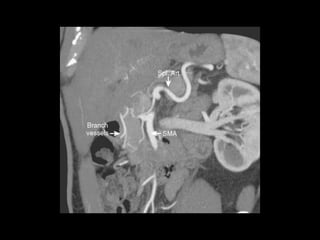

PÂNCREAS-VASOS

AORTA

TRONCO CELÍACO

MESENTÉRICA SUPERIOR

ESPLÊNICA

PANCREÁTICA DORSAL, MAGNA E TRANSVERSA

PANCREATICODUODENAIS SUP E INF

VEIA PORTA